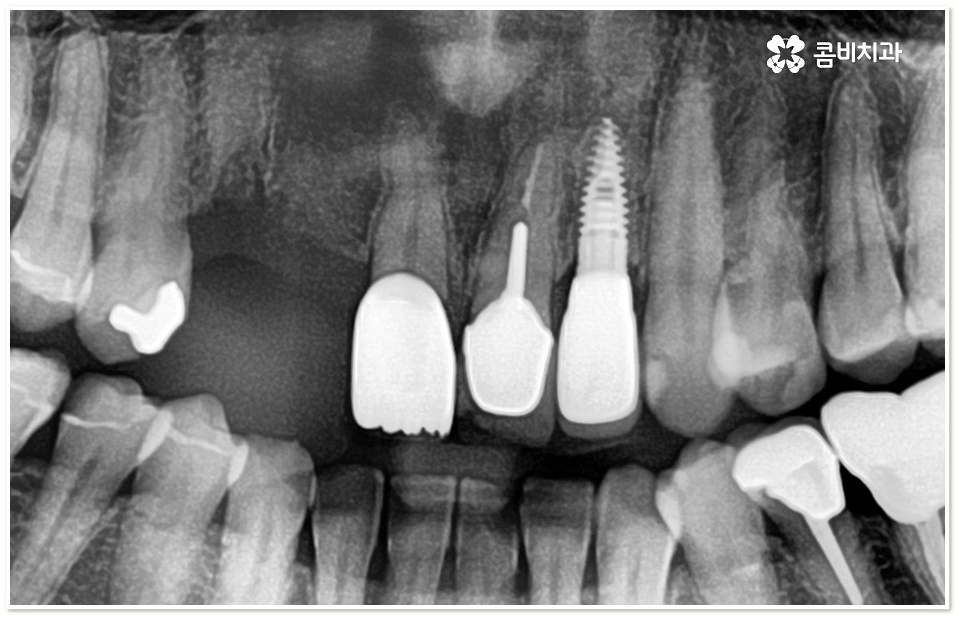

임플란트 시술은 상실된 치아를 대체하여 인체에 해가 없는 티타늄 소재로 된 인공치근을 잇몸뼈에 직접 식립한 후 기둥으로 인공치근과 인공치아를 연결하는 방식으로 진행되는데 앞니임플란트 시술을 받으면 씹는 힘도 자연 치아의 80~90% 가까이 회복할 수 있고 겉에서 보기에도 원래 자연 치아와 거의 흡사하게 수복이 되기 때문에 현대 임플란트 시술이 치아 상실을 대체하는 가장 대표적인 인공 치아 보철물로 자리매김 하고 있어요.

더욱이 앞니의 경우 말씀드린 것처럼 기능적인 부분 만큼 심미적인 부분까지 신경을 써서 주변 치아와 모양이나 색상, 투명도 등 모든 면에서 자연스럽게 어우러질 수 있는지 체크할 필요가 있기 때문에 앞니임플란트 시술이 어금니보다 까다로울 수 있어요.